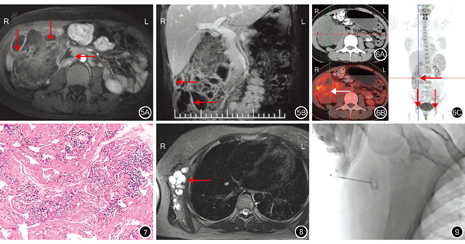

(6)淋巴管瘤的边界:16例患者中,15例淋巴管瘤边缘光整,与毗邻组织边界清晰;1例多房型淋巴管瘤与毗邻的十二指肠、胰头部及升结肠边界不清晰(图5)。

(8)淋巴管瘤的强化模式: 14例行增强扫描患者中,13例淋巴管瘤囊壁及间隔轻度强化(图2D),1例多房型淋巴管瘤中度强化(图5);淋巴管瘤内容物均无强化。

1例多房型淋巴管瘤呈18F-FDG不均匀摄取增加,内部见多发摄取缺损区,高摄取区与囊壁、间隔走行区基本一致,其代谢活性略高于肝脏,SUVmax=3.71,双侧腹股沟淋巴结FDG摄取增加,其余各部位未见明显18F-FDG摄取(图6)。

(5)18F-FDG PET/CT检查18F-FDG摄取:本研究中1例多房型淋巴管瘤呈FDG不均匀摄取增加,这提示淋巴管瘤虽然为良性囊性病变,但仍可以摄取FDG。Kwon等[4]报道右髂总动脉和右腹股沟区淋巴管瘤呈18F-FDG摄取增加(SUVmax=3.1)。Ji和Kuang[5]报道脾脏淋巴管瘤呈轻度18F-FDG摄取增加(SUVmax=3.0)。此外也有文献报道,肠系膜、腹膜后间隙和脾脏淋巴管瘤没有出现18F-FDG摄取的情况[6,7,8]。肿瘤、炎性病变活动期及肉芽肿形成期均可以显著摄取FDG[24]。本研究中淋巴管瘤病理学检查提示未见感染,摄取FDG的机制可能与淋巴细胞的特异性有关。此外,18F-FDG PET/CT检查还可以弥补CT或MRI基于形态学改变和局部检查的不足[25]。